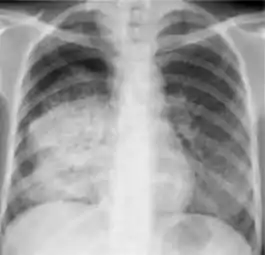

Dense homogenous opacity in right, middle and lower lobe of primary pulmonary TB.

Chest x-ray showing patchy opacification on the upper right and mid-zone lung with fibrotic shadows, as well as bilateral hilar lymphadenopathy.